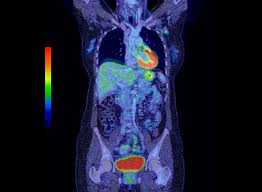

Results from a recent retrospective study conducted by memorial sloan kettering cancer center investigators suggest that pet/ct scanning might offer the most efficient and effective detection of newly diagnosed breast cancer that has spread to the bone.

Ultrasound may also be used to locate the position of a tumor in order to guide the doctor during a biopsy or aspiration procedure. Sandy,i asked my onc.he says ct's can pick up breast cancer depending part on location.i guess it's like real estate,location,location,location,lol.but seriously theradiologist who read my lung ct in november wrote in his report specifically there was no evidence of breast cancer.i guess due to them watching a lymph gland for 2 years on my rt breast.it was fine in mammogram in october so i am now back to yearly,thank god,andib She spent months, getting more surgery, chemotherapy and radiation and 8 months later and she was cleared for work. Ct scans can help doctors: A pet/ct scan is a newer technology used to create images of the body's cells as they work. These scans expose you to more. Doctors use a computed tomography (ct) scan, also called a cat scan, to find cancer. Results from a recent retrospective study conducted by memorial sloan kettering cancer center investigators suggest that pet/ct scanning might offer the most efficient and effective detection of newly diagnosed breast cancer that has spread to the bone. Are they as reliable in detecting breast cancer as a regular mammogram? Benefits of a ct scan. It is common for patients to receive a diagnosis for cancer of unknown primary. This test is most often used to look at the chest and/or belly (abdomen) to see if breast cancer has spread to other organs. Should you get a ct scan to detect possible tumors?

Learn more about it on our blog. Ct scans can be misread or misinterpreted. Learn the stage of your cancer. In some instances, cancers may not show on the scan. The answer is yes, and american health imaging can help. Mammograms take advantage of the fact. Pet scan for breast cancer. A pet/ct scan is a newer technology used to create images of the body's cells as they work. A ct scan can be wrong: If the cancer is thought to have spread, doctors can use imaging tests (tests that create pictures of the inside of the body) to help find out if or where a cancer has spread. I freaking out today though because i have a hard area in my left breast. Benefits of a ct scan. Some researchers are studying the usefulness of pet (positron emission tomography)/ct scans in staging inflammatory breast cancer.